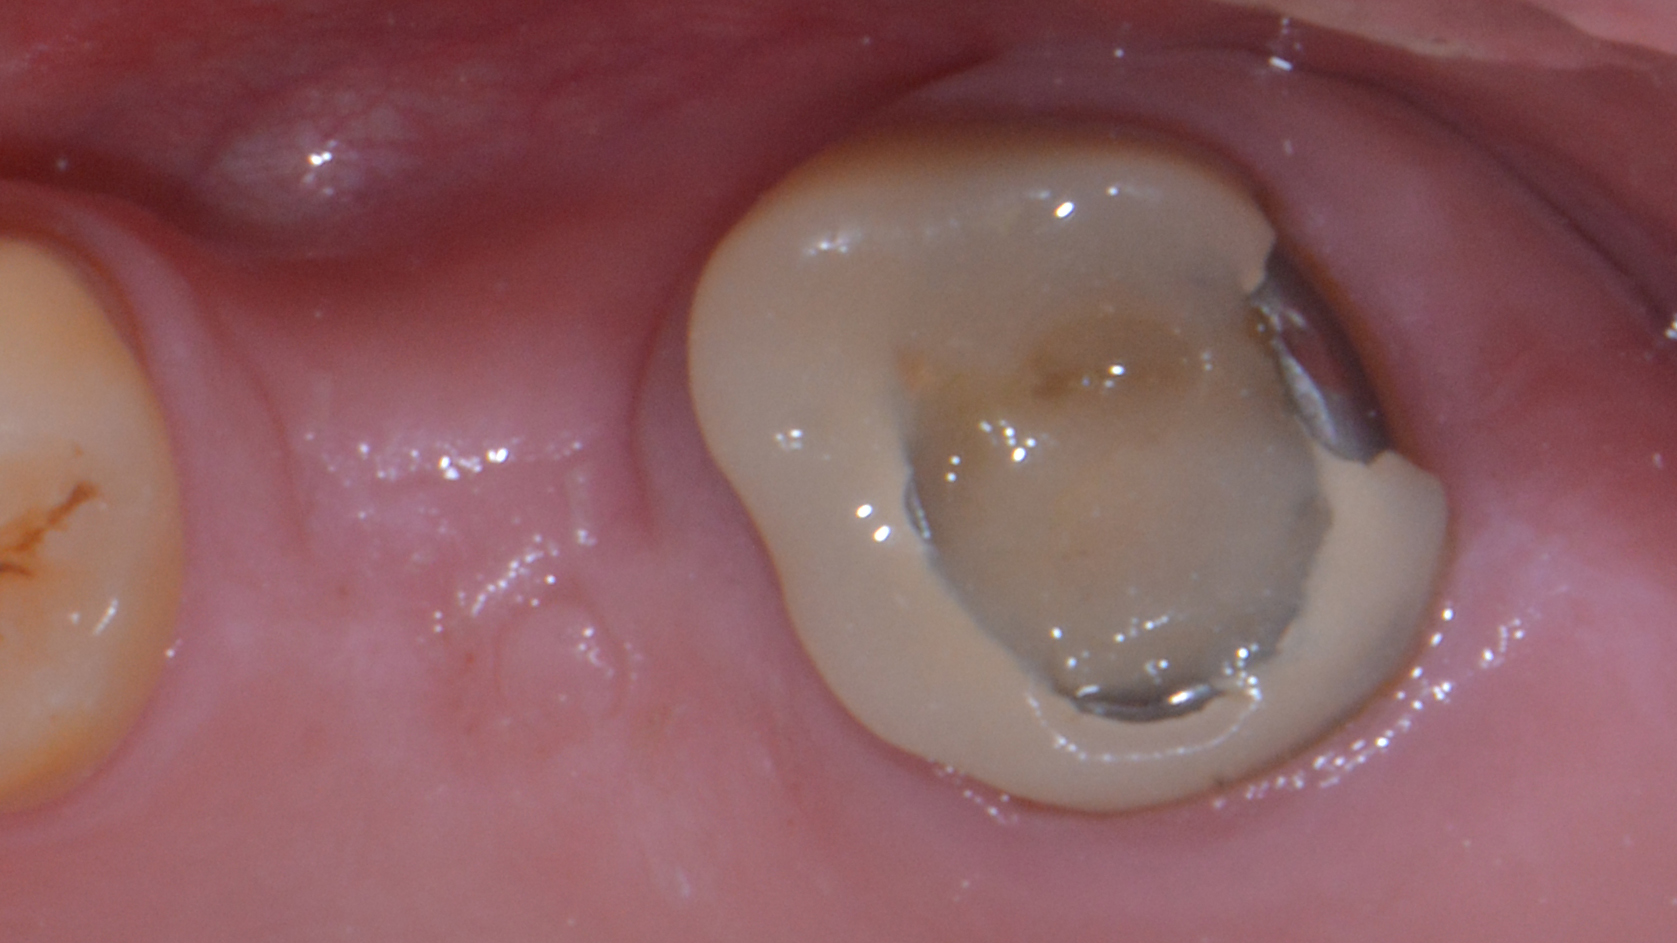

Altro paziente, 24 anni.

Guarda un po’: la vedi l’imprecisione del manufatto?

Questa corona è stata fatta circa un anno fa da uno dei dentisti più blasonati della mia città. Studio nella via più chic. Assolutamente l’opposto di un low cost.

Il paziente si è rivolto a noi perché ha notato che la corona aveva dei problemi e il dentista l’ha ritoccata (cito) “circa cinquanta volte” prima di cementarla. Ti mostro anche la foto:

Dopo qualche mese l’ha bucata per ritrattare il dente e l’ha otturata.

Ti sembra che fosse il caso di lasciare in bocca questa cosa?

Che ad un anno dal confezionamento (e dal pagamento del paziente) si presenta così?

In un paziente di 24 anni?

O magari sarebbe stato meglio rifarla?